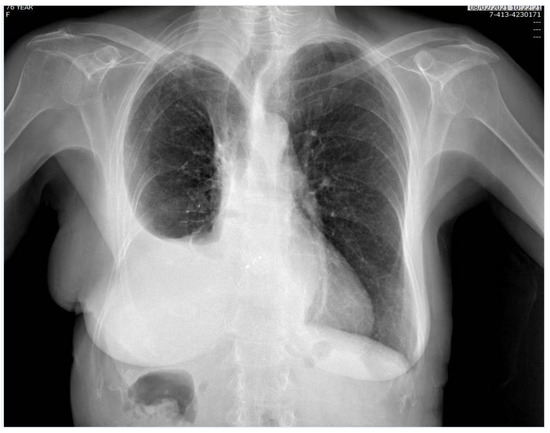

Figure 3.

Chest X-ray, performed one month after surgery.

The patient was referred to the Cardiac Catheterization Laboratory for percutaneous closure of PFO via a transesophageal echocardiogram-guided Amplatzer Multi-Fenestrated Septal Occluder (Video S3). The patient was able to stand up with no symptoms the day after implantation, and she was discharged on the third postimplantation day. All the details concerning the hospital stay are reported in Table 1. One-month follow-up examination showed a good and stable condition (Figure 3). With regard to the oncological follow-up, the histological examination led to the diagnosis of invasive adenocarcinoma with predominant solid pattern pT4N1 G3; the comprehensive molecular profiling did not reveal any mutation. According to the pathological stage, the patient was admittable to adjuvant chemotherapy; the performance status after surgery did not allow the administration of systemic therapy. The patient underwent a total body CT scan six months after surgery which detected local cancer progression and multiple bone metastases.